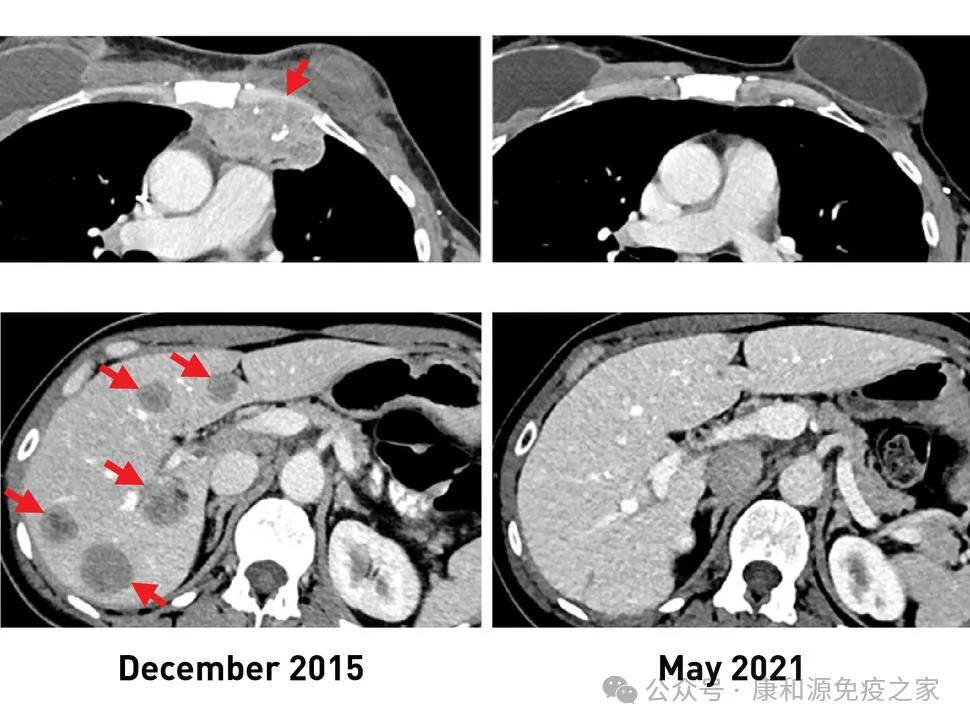

tils细胞疗法打破实体瘤治疗瓶颈!5个月肿瘤全部消失!